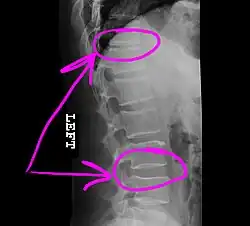

Example of how a telestrator might annotate a medical image shared during a telemedicine session